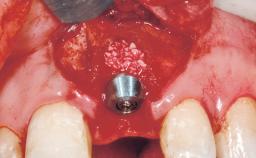

A 42-year-old female patient was referred to our clinic at the School of Dentistry of the University of São Paulo in November 2004, presenting a deficient restoration in the upper left central incisor. The clinical examination revealed no gingival retraction or any signs of gingival inflammation and, therefore, previous periodontal treatment was not considered. The patient presented a high lip line at full smile and a thin tissue biotype. This combination characterized a high-risk situation from an anatomic point of view, which required careful preoperative planning and cautious surgical execution.

Placement Protocol Immediate implant placement

Tooth Site Maxillary incisor or canine

Socket Morphology Single-root socket

Socket Integrity Sufficient, with intact bone walls